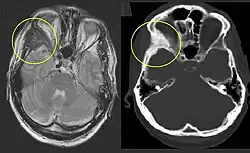

On x-ray, fibrous dysplasia appears as bubbly lytic lesions, or a ground glass appearance. Computerized tomography (CT) or magnetic resonance imaging (MRI) scans may be used to determine how extensively bones are affected. CT can better demonstrate the typical "ground glass" appearance, which is a highly specific radiological finding, while MRI can show cystic areas with fluid contents.[15] A bone scan uses radioactive tracers, which are injected into your bloodstream. The damaged parts of bones take up more of the tracer, which show up more brightly on the scan. A biopsy, which uses a hollow needle to remove a small piece of the affected bone for laboratory analysis, can diagnose fibrous dysplasia definitely.